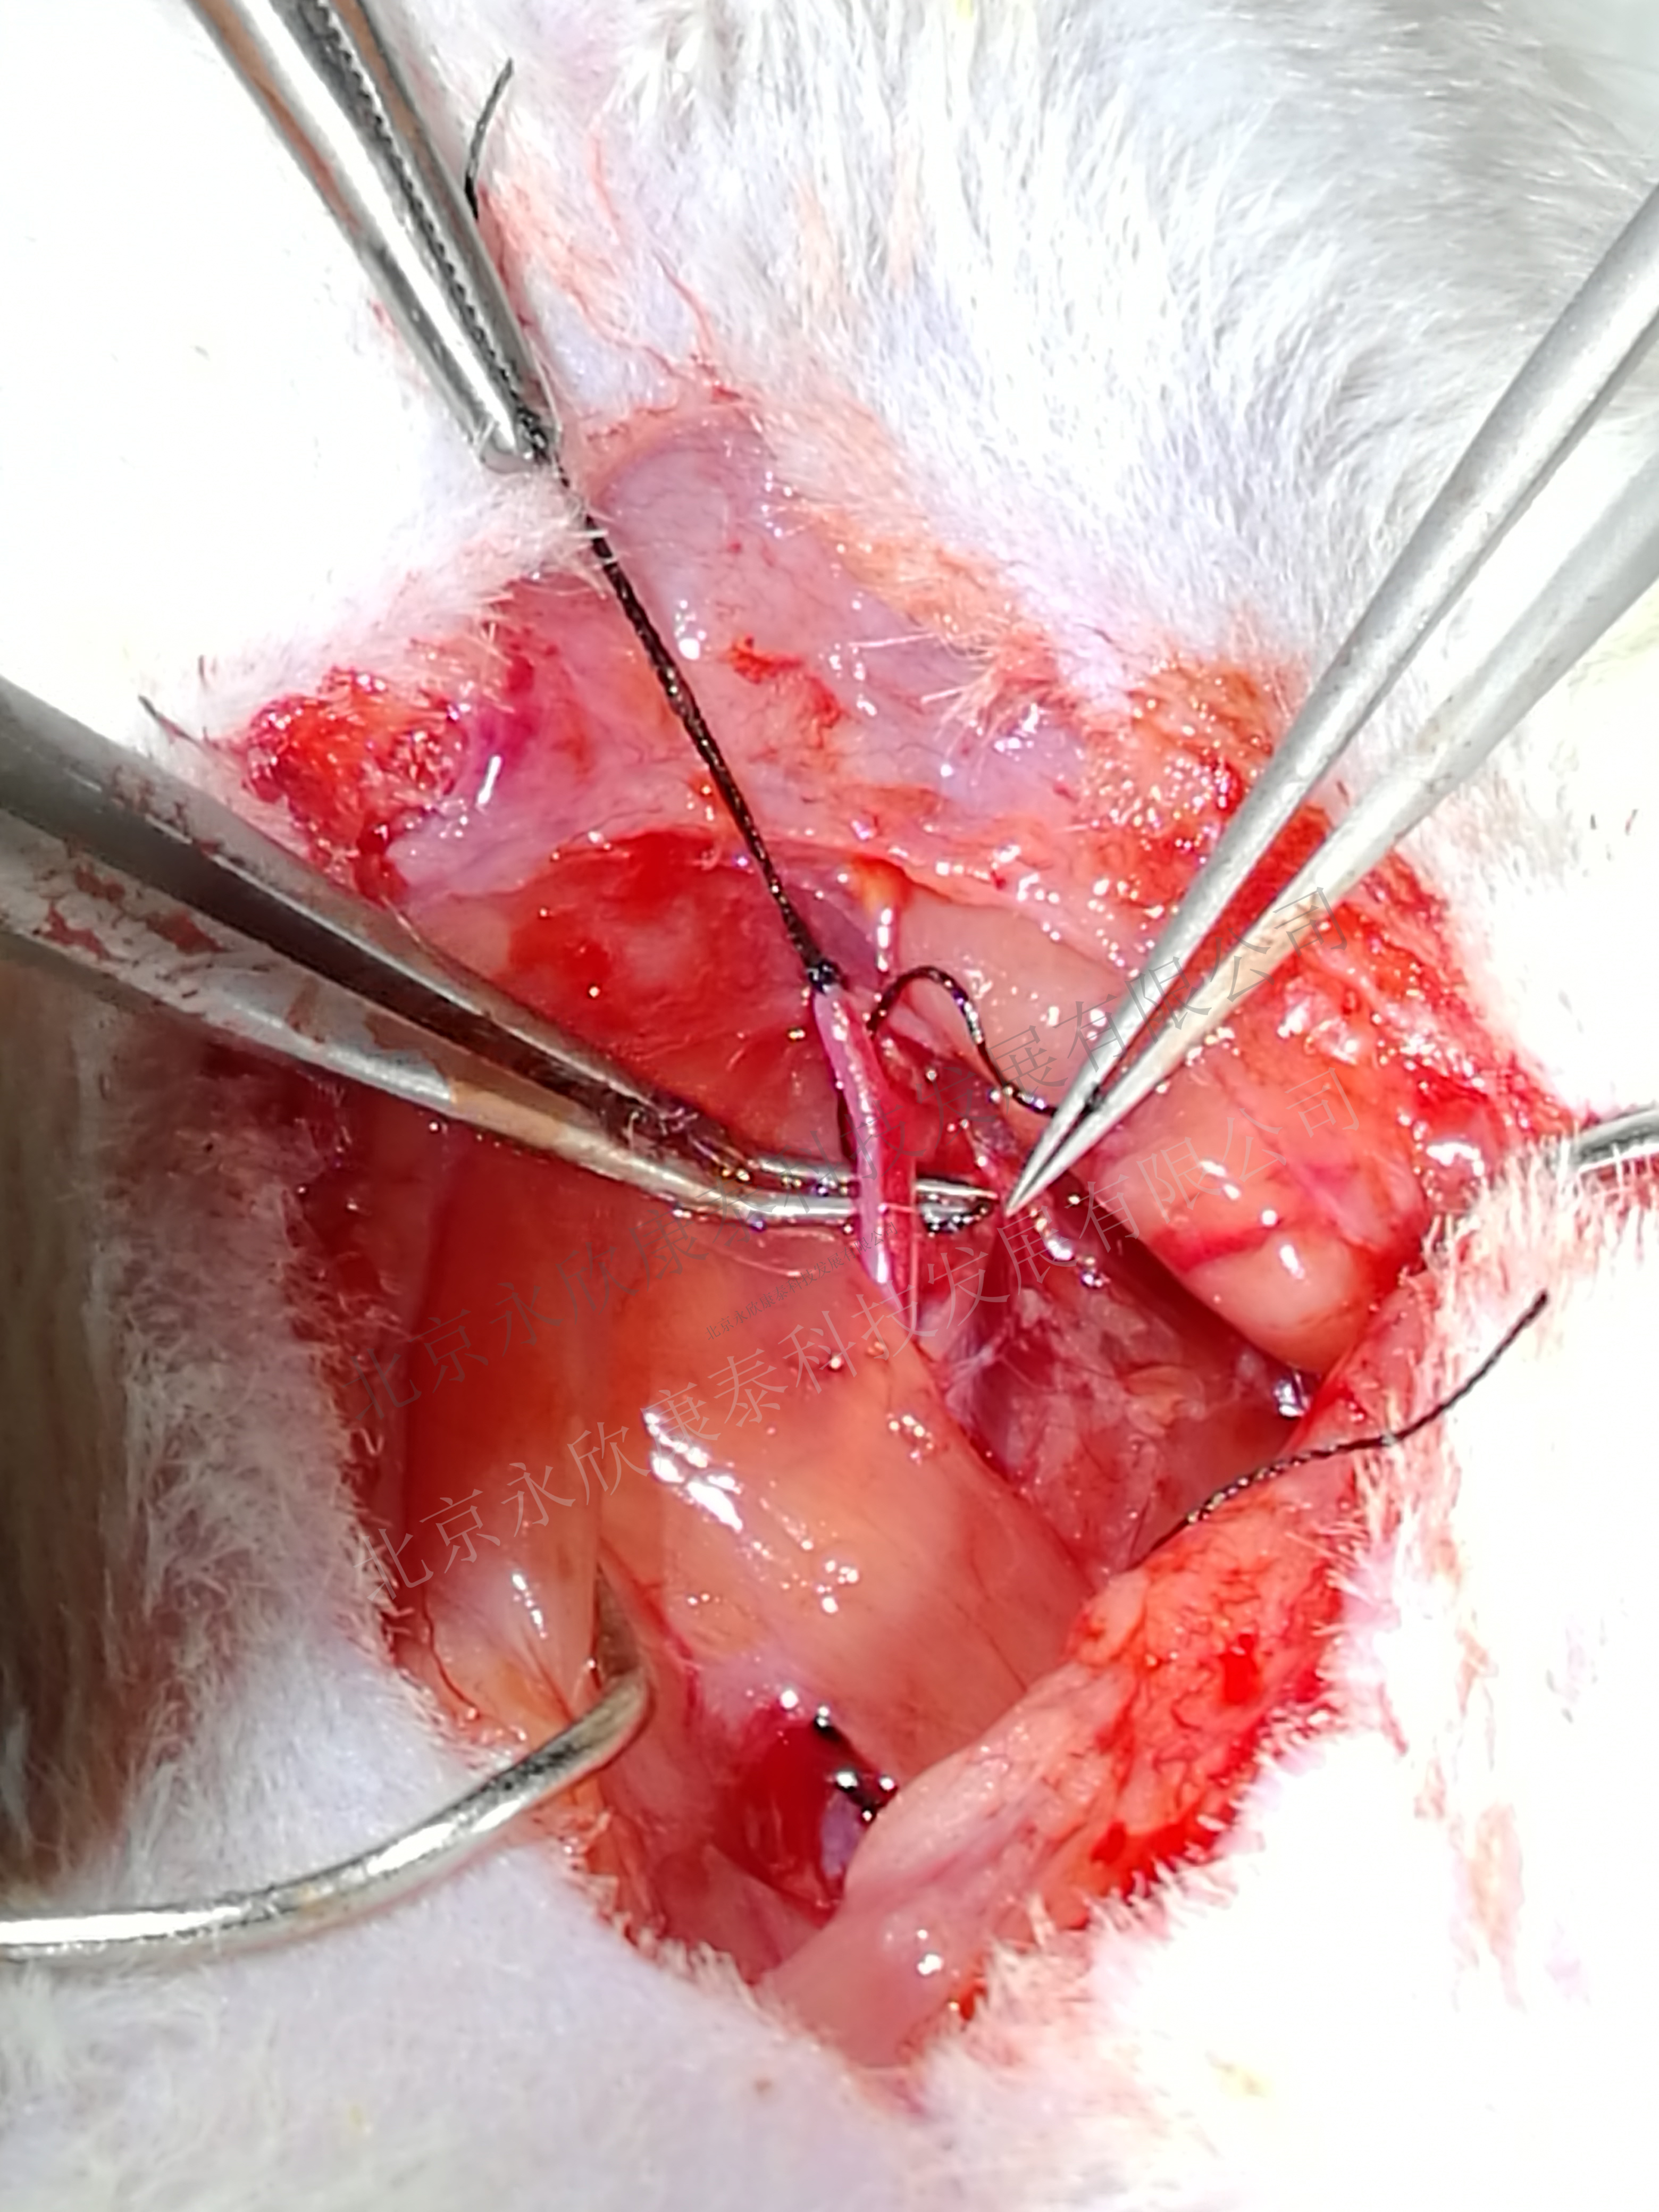

1、球囊拉伤大鼠颈动脉,致颈动脉斑块模型

2、特殊球囊、手术快速、成活率达到90%

4、动脉取材、石蜡、冰冻病理切片

5、血管油红染色、马松masson染色 HE染色、免疫组化、荧光